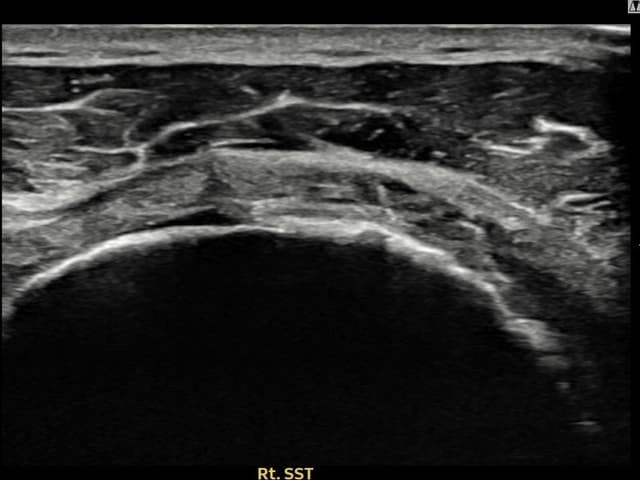

[촬영시기:23.09.01~23.11.03]

[어깨인대 축소봉합술] 우측 어깨 통증이 수개월간 지속되어 내원하셨습니다.